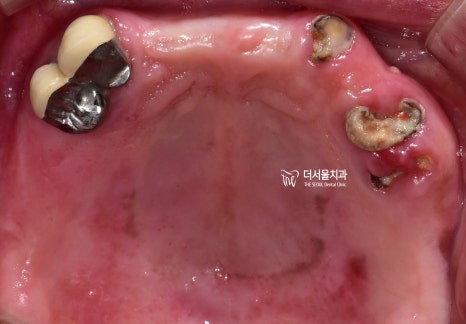

상악에는 전체 틀니를 해드려도

환자들께서 큰 불편함 없이 잘 쓰시는 편입니다.

그래서, 상악에는 남아있는 잔존치아를

발치를 한 뒤에 전체 틀니를 해드리기로 했으며

『틀니 치료 결과』

틀니를 장착 했을 때,

첫번째로 고려해야 될 것은

‘편안함’ 입니다.

연조직이랑 맞닿아서 유지력을 얻기 때문에

정말 신중히 제작을 해야 되는데

이렇게 만들어드린 뒤에, 인상 채득을 거쳐

사진에서 보실 수 있는 것 처럼

상악 전체 틀니가 완성이 됩니다.